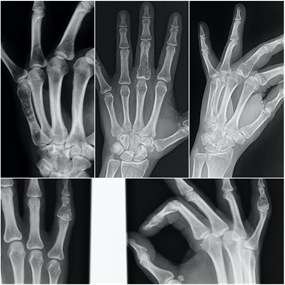

El Encondroma es una lesión que encontramos frecuentemente en las radiografías. En muchas ocasiones es una lesión asintomática. Es habitual encontrarlos en pacientes jóvenes como un hallazgo casual al realizar una radiografía por otro motivo. Supone la proliferación de cartílago maduro dentro del hueso.

El encondroma es el tumor primario más frecuente en las manos, particularmente en las falanges proximales. También es frecuente en la tibia, en el tercio superior del fémur y en el húmero.En las radiografías solemos observar una lesión bien delimitada con matriz variable, desde osteolítica hasta intensamente mineralizada cuya imagen característica es de calcificaciones puntiformes, en grumos, anillos o arcos. En los huesos pequeños pueden ser muy expansivos, adelgazando la cortical del hueso, provocando dolor y fracturas patológicas. En huesos grandes no suele haber expansión del las corticales, pudiendo aumentar su tamaño intramedularmente y avanzar hacia la diáfisis.

El encondroma asintomático habitualmente no precisa tratamiento. Cuando presentan gran tamaño, rompen las corticales del hueso o afectan a las partes blandas hay que descartar la degeneración maligna o condrosarcoma y deben evaluarse de forma especializada.